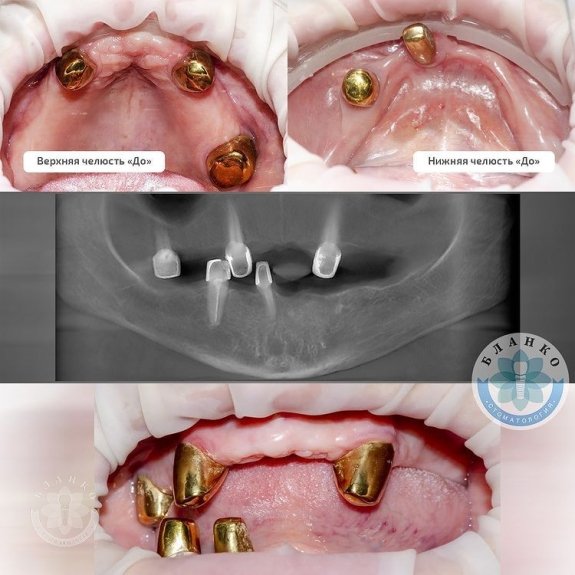

В данной ситуации в первое посещение были удалены оставшиеся зубы, пораженные пародонтитом ( 5 штук ).

Сразу установлено 10 имплантов.

Через 4 месяца постоянное протезирование двумя несъёмными конструкциями на верхней и нижней челюсти.